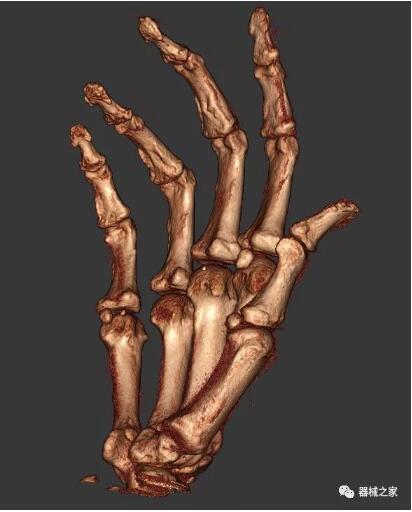

以下是這些“特立獨(dú)行”的CT所拍出來(lái)的圖像: